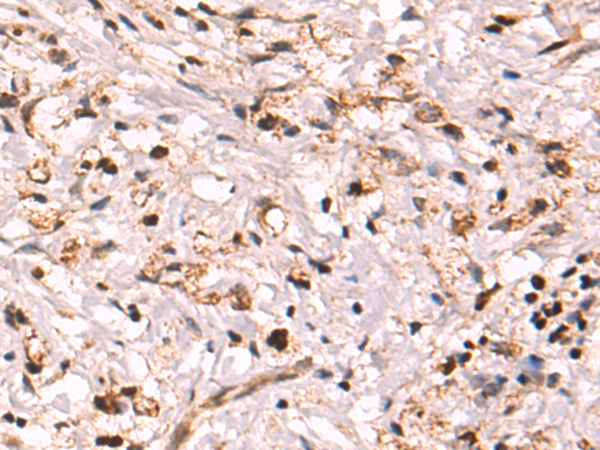

分类: 科研抗体货号: P02516别名: VPS20应用: WB,IHC反应种属: Human, Mouse